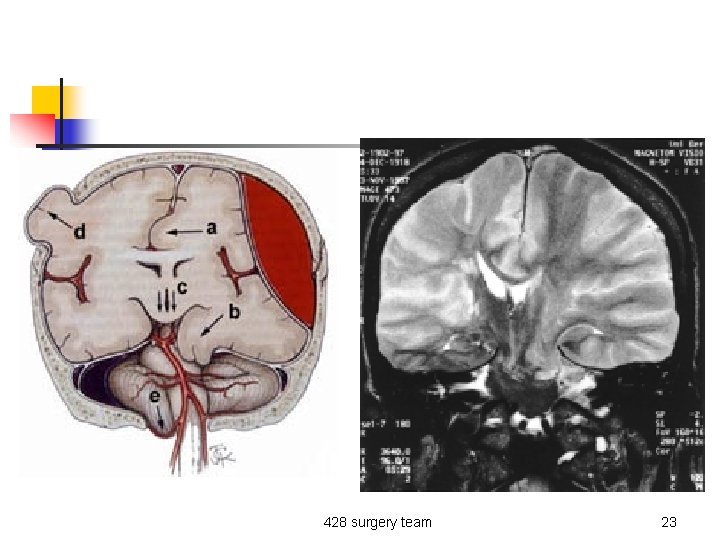

n Neurological: n n n Pupillary dilation Hemiplegia Cranial nerve deficit 428 surgery team 21

428 surgery team 23

n If there is a mass compressing the 3 rd nerve So, ipsilateral pupil dilation and compression on the brain stem will give you contralateral hemiplasia ”weakness”. missinglink. ucsf. edu/. . . / Tentorial. Notch. Blum. jpg 428 surgery team 24

Trans-tentorial herniation: - Ipsilateral dilated pupil - Contra-lateral weakness 428 surgery team 25